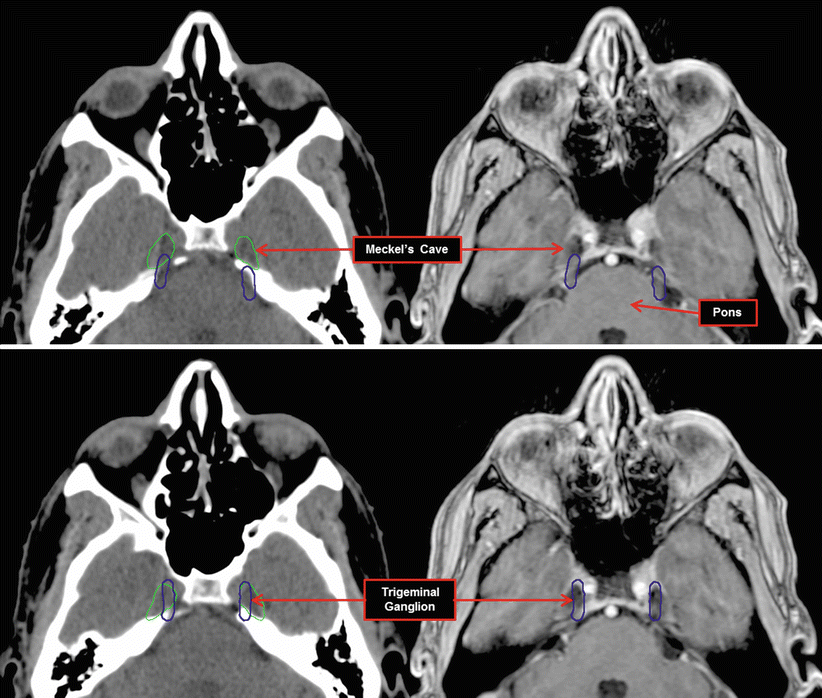

A) CT scan (axial section) showing a calcific, punctate lesion Where Is Meckel S Cave Located Trigeminal cave, also known as meckel’s cave or the trigeminal impression, is a depression on the front surface of the apex of the petrous temporal bone. The sellar and parasellar areas,. Meckel's cave is a gateway of prime significance, leading into various regions of the skull base. It faces the middle cranial fossa. Where Is Meckel S Cave Located.

Meckel's cave is shown on this T2 weighted axial brain MRI for a Where Is Meckel S Cave Located Meckel's cave is a gateway of prime significance, leading into various regions of the skull base. It faces the middle cranial fossa. Trigeminal cave, also known as meckel’s cave or the trigeminal impression, is a depression on the front surface of the apex of the petrous temporal bone. The sellar and parasellar areas,. Where Is Meckel S Cave Located.